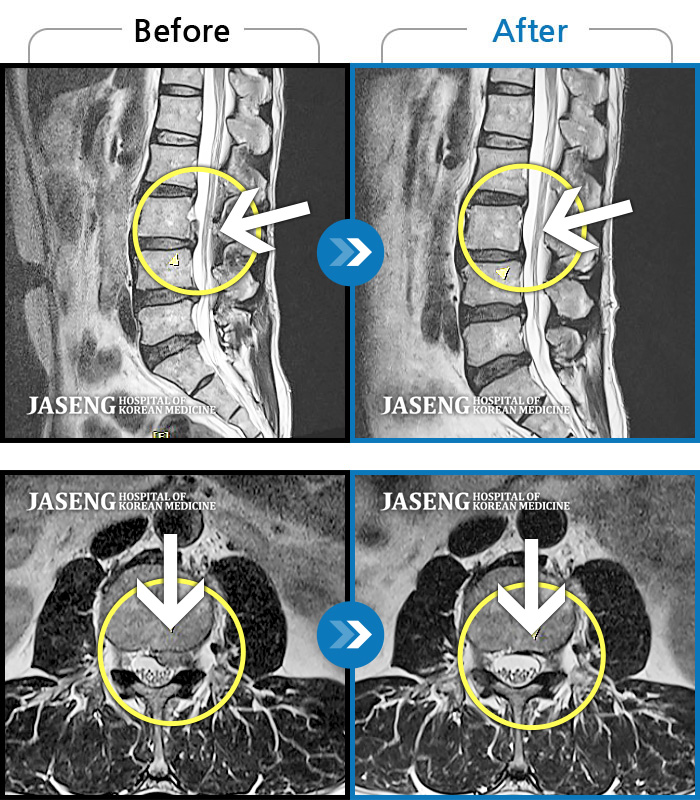

MRI 치료사례

허리 양측부터 골반까지 묵직한 통증, 좌측 하지 후면으로 이어지는 당기는 통증